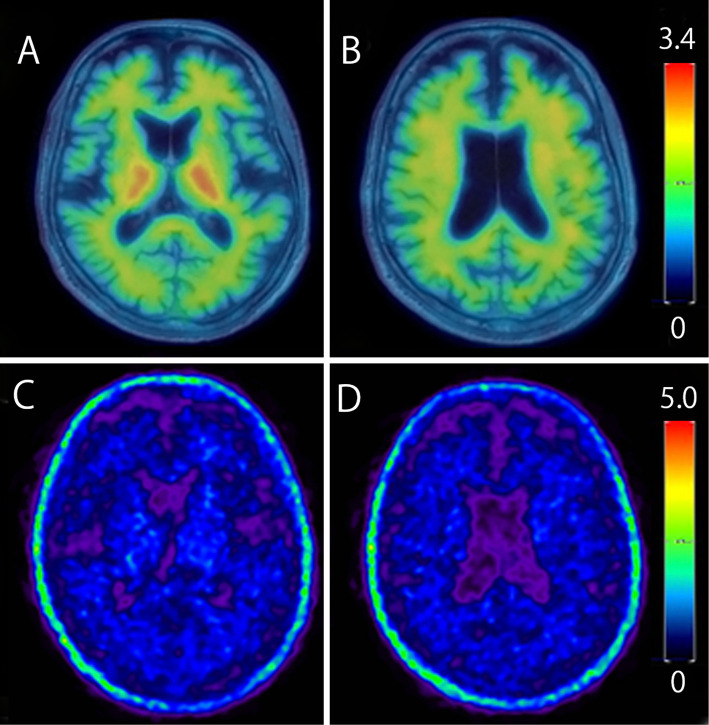

A 47-year-old man with a family history of juvenile dementia in his mother presented with memory loss and cognitive decline. Neuropsychological tests revealed impaired orientation, working memory, and apraxia. Magnetic resonance imaging revealed diffuse brain atrophy, and fluorodeoxyglucose positron emission tomography (PET) showed hypometabolism in the bilateral parietal lobes, posterior cingulate gyri, and precuneus, suggestive of Alzheimer's disease. However, amyloid-beta and tau PET scans were negative. Genetic testing revealed an abnormal repeat insertion in the prion protein gene, confirming inherited prion disease. This case highlights the need to consider inherited prion disease in the differential diagnosis of early-onset familial dementia.

Abstract Image